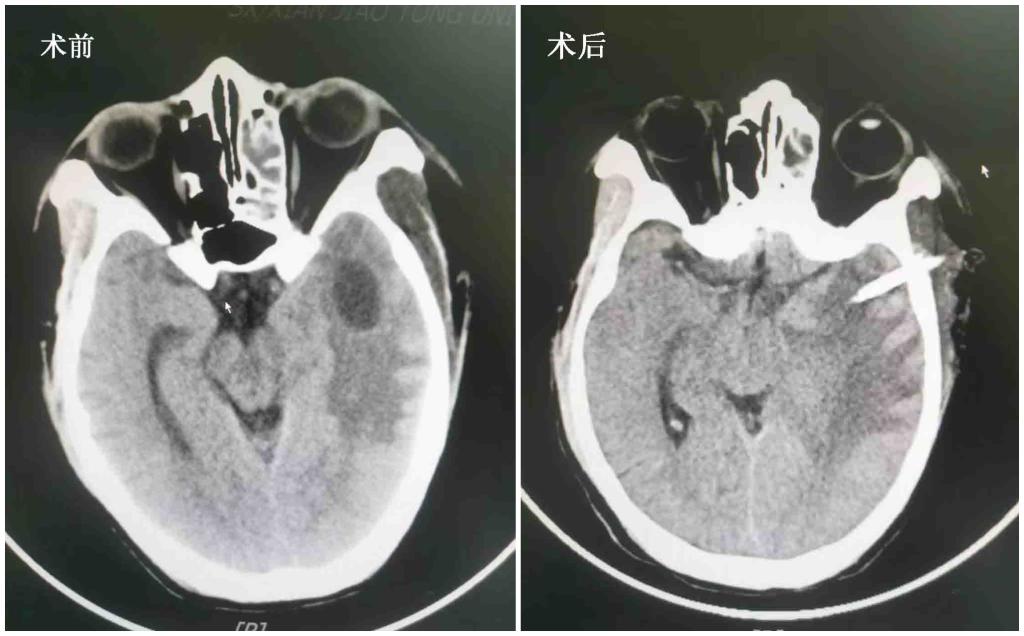

入院后完善颅脑影像学检查,考虑鼻咽恶性肿瘤性病变并颅内侵犯,并颅内脓肿形成。期间头痛进展性加重,为明确是否存在颅内感染,腰穿外送脑脊液NGS检查提示厌氧菌感染并颅高压(260mmH2O),请药学部会诊后予以万古霉素+美罗培南抗感染治疗,同时复查颅脑CT有脑疝征象,请神经外科、耳鼻喉科联合制定方案后,我院神经外科张熙副主任医师行立体定向脑切开引流术,术后患者头痛明显缓解,体温逐渐下降,眼外肌麻痹明显改善。

图1 立体定向脑切开引流术前术后对比,术后3天脓腔缩小,脑水肿减轻。